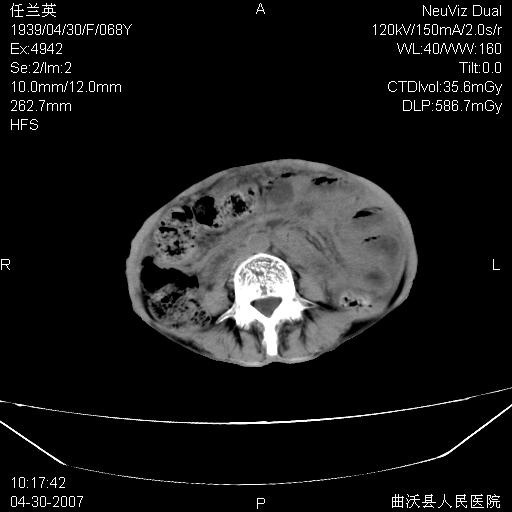

患者,女,68岁,感觉腹部憋涨发硬数天,查b超发现左盆腔有囊性肿物和少量腹水,行ct检查

1.考虑卵巢肿瘤并腹腔广泛性转移可能性大;

2.腹盆腔少量积液。

支持左侧卵巢恶性肿瘤伴网膜、腹膜广泛转移。

支持:左侧卵巢恶性肿瘤伴网膜、腹膜 腹膜后(淋巴结)广泛转移。

难的一见 典型 - 网膜饼  冰冻骨盆 可以当教学片了